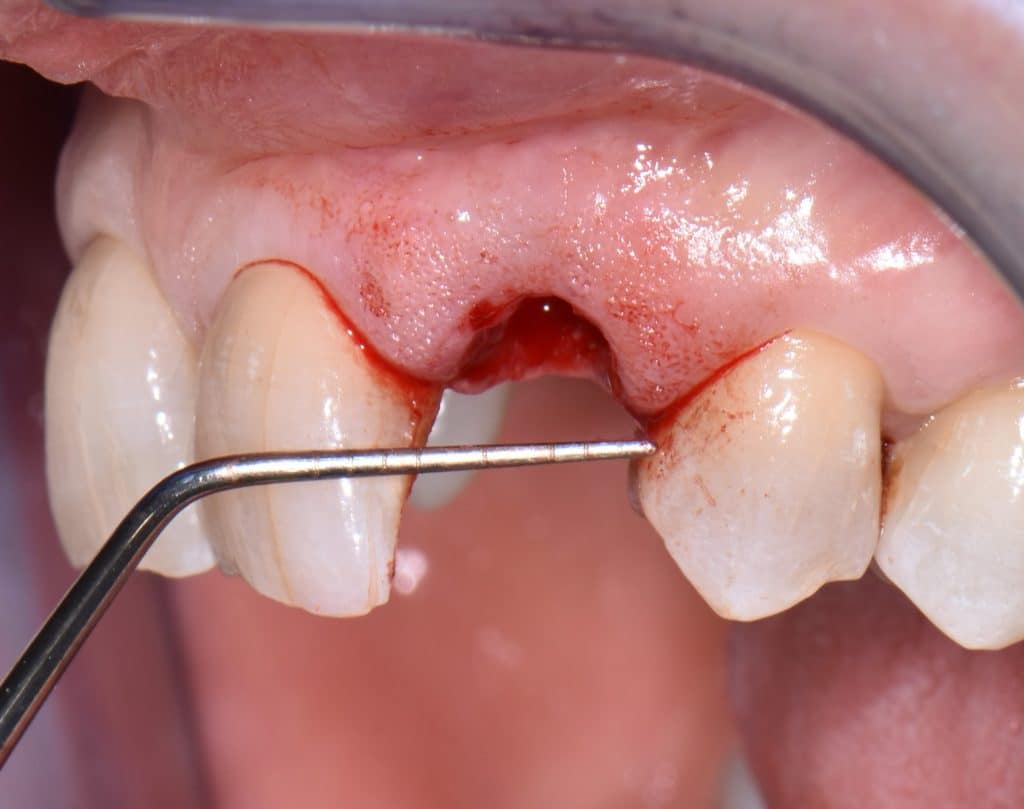

La pz N.G. di anni 52 (ASA 1) viene visitata nel mese di settembre 2017 per la mobilità ed inestetismo dell’elemento protesico 22, (foto iniziali sequenza 1) si evidenzia una frattura parziale della radice, si decide per l’estrazione ( foto sequenza 2) e sostituzione dell’elemento con un restauro implanto-protesico. Purtroppo la scarsa quota ossea apicale all’alveolo post-estrattivo (foto 2 rx) e l’alta valenza estetica dell’elemento ci rende cauti e si programma una socket preservation post estrattiva con l’ausilio delle membrane di prf (foto prf e socket sequenza 3 e 4). Durente i 5 mesi di guarigione la pz porta una protesi parziale mobile (foto 5,2) , a guarigione del sito post estrattivo si evidenzia una buona conservazione dei volumi osseo-gengivali,(foto guarigione sequenza 6) se pur presente una recessione distale all’elemnto 21.Nel mese di febbraio 2018 si procede all’inserimento di un impianto max-stability 3,75x12mm disegnando un lembo anticipato palatino per consentire un aumento dei tessuti vestibolari suturando con tecnica rool flap e trasformando l’elemento parziale mobile in una corona singola a carico immediato sul moncone temporameo applicando i concetti protesici bopt , (foto impianto moncone protesi provvisoria sequenza foto 7-8-9). Durante il periodo di maturazione dei tessuti molli vengono apportate opportune modifiche ai profili del provvisorio al fine di dare maggior spazio al tessuto gengivale, ( fotosequenza 10).Dopo circa 2 mesi dal protesizzazione provvisoria si è proceduto alla realizzazione del manufatto protesico con tecnica chair side sirona con l’ausilio del t-base (foto sequenza 11-12-13), realizzando in una sola seduta una corona in disilicato, ottenendo un risultato più che soddisfacente (Foto 14). Nel controllo a 3 mesi dal carico definitivo si apprezza la perfetta conservazione dei livelli ossei e gengivali. (foto sequenza 15).concludo con un follow up a 18 . Tengo a sottolineare che un caso come questo è stato conducibile con buoni risultati solo grazie alla piena fiducia della pz e alla sua massima motivazione e collaborazione. Ad oggi la pz sorride soddisfatta del risultato. E questo rappresenta la massima ricompensa di chi dedica tutto se stesso alla professione.